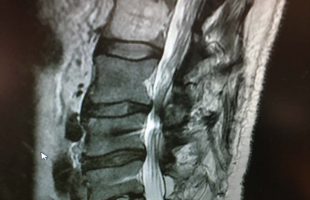

Η Μα. Φο. 26 ετών προ δεκαετίας υποβλήθηκε (αλλαχού) σε χειρουργική επέμβαση στη θωρακο-οσφυική περιοχή της σπονδυλικής στήλης (Σ.Σ.). Η επέμβαση εγένετο προκειμένου να αφαιρεθεί καλοήθης νεοπλασματική εξεργασία (επενδύμωμα) η οποία της είχε προκαλέσει σφιγκτηριακές και νευρολογικές διαταραχές στα κάτω άκρα. Προκειμένου να γίνει εξαίρεση της νεοπλασματικής βλάβης, πραγματοποιήθηκε ευρεία αφαίρεση οπίσθιων στηρικτικών στοιχείων τωνRead more →